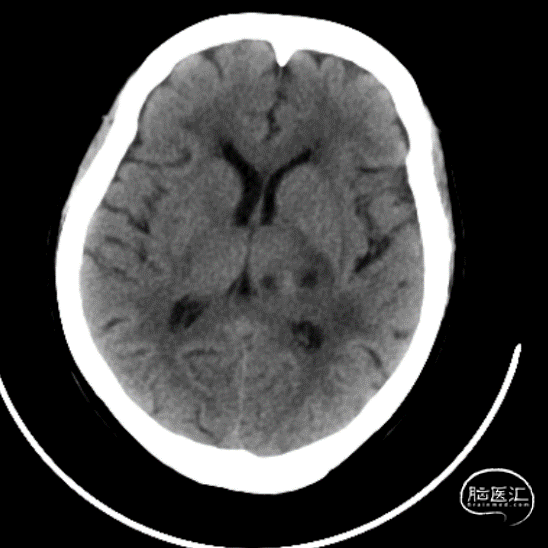

术后影像

Post-op-D4

Post-op-D8

Post-op-D15